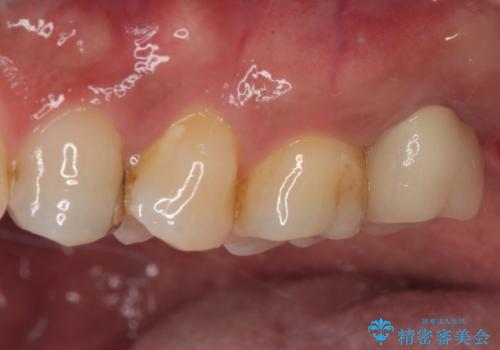

骨の透過像が非常に大きく、根管も大きく削られていたため、歯根破折による抜歯の可能性がありましたが、根管治療可能な状態でした。

初回治療後には速やかに痛みが改善され、非常に大きかったレントゲンでの骨透過像も改善されました。